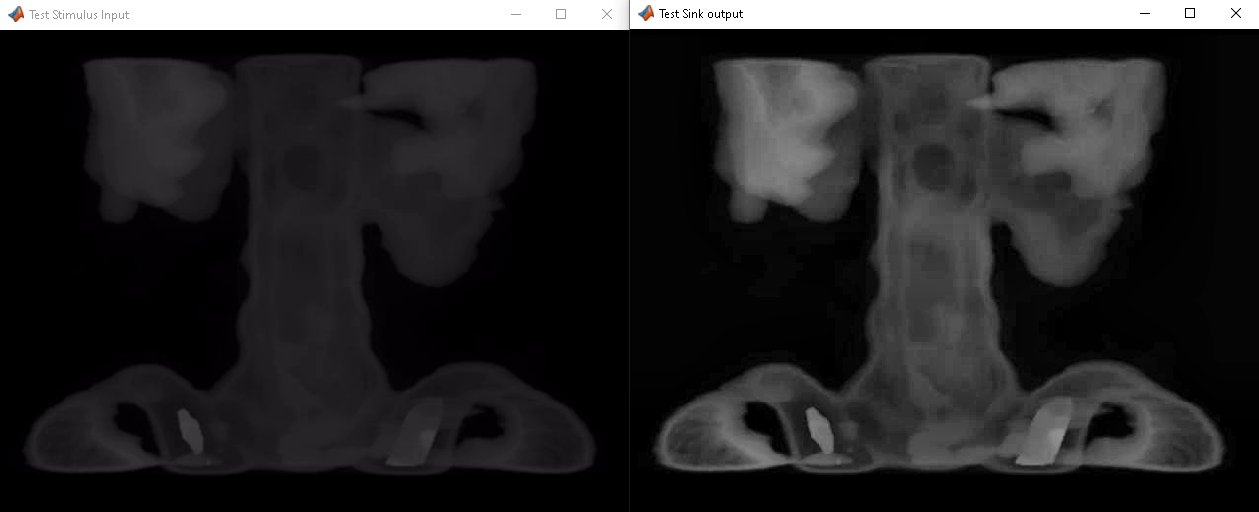

Если у вас есть лицензия HDL Verifier, можно использовать FPGA в функции цикла, чтобы моделировать проект HDL на плате FPGA. Блоки на этой странице обеспечивают улучшения КПД для потоковой передачи пиксельных данных через Simulink® к интерфейсу платы FPGA. HDL Verifier также позволяет cosimulate модель Simulink с проектом HDL, запускающимся в стороннем средстве моделирования.